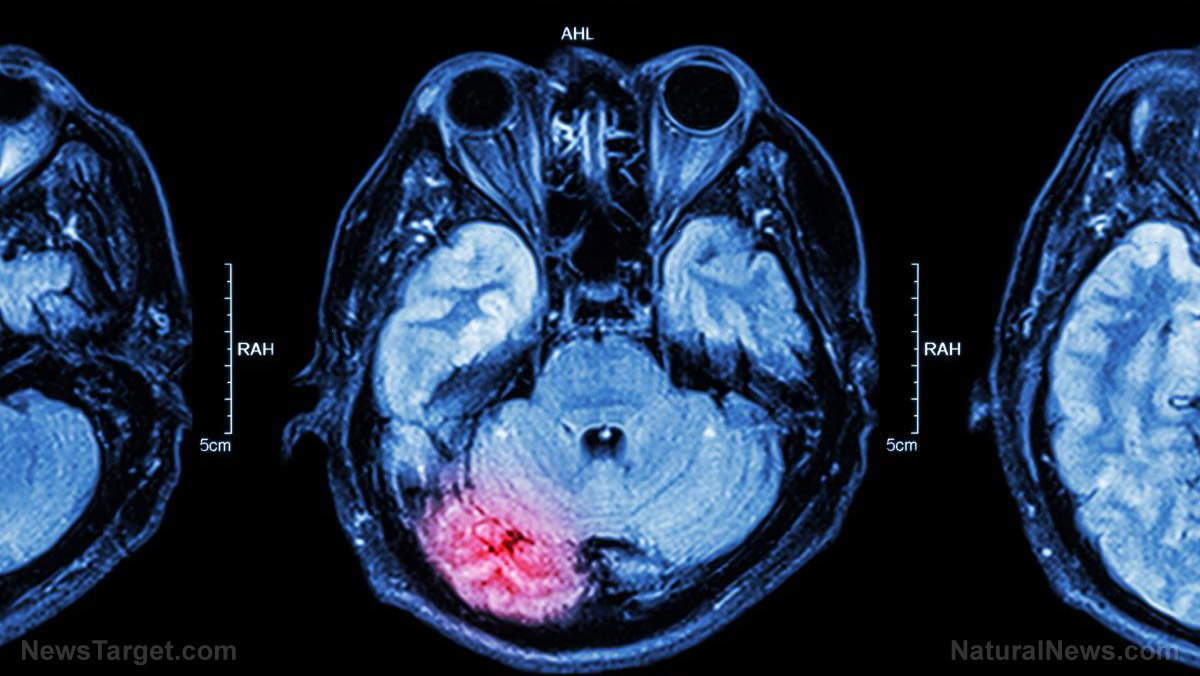

Female brains are delicate and more vulnerable to concussions than the brains of men – study

A recent study by neuroscientists from Penn Medicine, for example, found that women have leaner nerve fibers in the brain, making them more susceptible to concussions than men. The study was published in the journal Experimental Neurology.

The research team performed several tests on rat and human neuronal cells, and found that female axons – long, slim parts of the neuron that are responsible for relaying messages and are viewed as the brain’s “electric grid” – are smaller than men’s. Female brain axons also contain fewer microtubules, which are like the pathways that transport molecules up and down the axons.

The scientists found that when exerting an equal amount of pressure on female and male axons to simulate a traumatic brain injury, the female axons were more likely to break.

When someone suffers a traumatic blow to the head, the axons are stretched at a very rapid rate. While the axons typically stay intact, their microtubules can break under the strain. The faster they stretch, the stiffer the crosslinking proteins known as tau become. This transfers high stress onto the microtubule that can result in them rupturing, setting off a molecular imbalance.

Once the brain’s “transport system” is disrupted in this way, things quickly go haywire, creating a buildup of sodium and calcium ions. When calcium levels reach a certain level, a self-destruct process is triggered, unleashing protein-breaking enzymes which damage the structure of the axon.

Tests revealed that 24 hours after such an injury, female axons exhibit significantly more swelling and a greater loss of calcium signaling function than male axons.